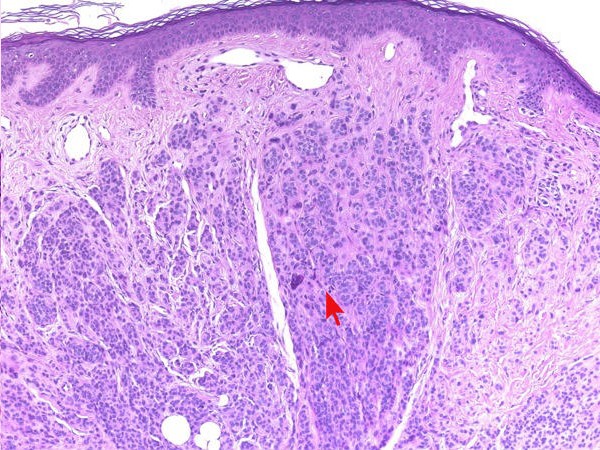

Histologische

variantenDe naevi naevocellularis worden ingedeeld in 3 histologische

varianten

-

junctional naevus (naevus naevocellularis

marginalis): opeenhoping van naevuscellen in de epidermis

dermal

/

intradermal naevus (naevus naevocellularis dermalis):

opeenhoping van naevuscellen in de dermis

compound naevus

(naevus naevocellularis epidermo-dermalis): opeenhoping van naevuscellen in

zowel dermis als epidermis

Zie ook de ingescande PA-coupes (

compound

naevus) van de

afdeling

pathologie van de University of Toronto.